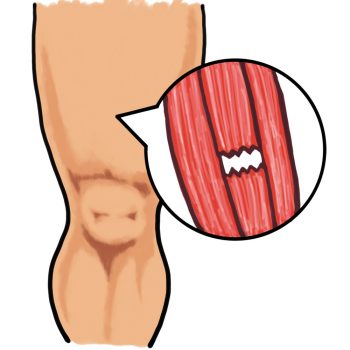

■ 肉離れは「急にくる」ことが多い

肉離れは、

ダッシュやジャンプの瞬間に起こることが多いですが、

実は

・疲労の蓄積

・柔軟性不足

・フォームの崩れ

が背景にあることがほとんどです。

「急に切れた感じがした」

と表現される方もいますが、

体はずっとサインを出していた可能性があります。

■ 肉離れの再発は焦りが原因

肉離れの場合、

「もう痛くないから走れそう」

と早期復帰してしまうケースがあります。

ですが、

筋繊維は完全には修復していないこともあります。

柔軟性が戻らないまま

負荷をかければ、

同じ場所を再び傷めます。